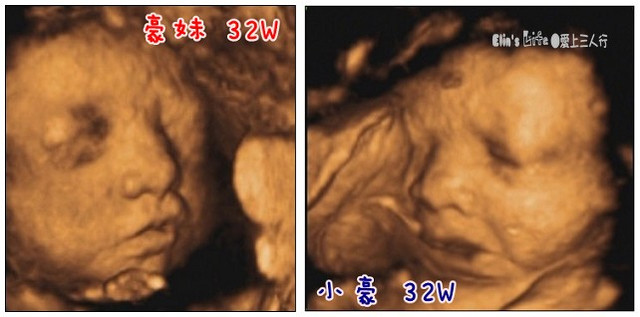

32w1d,4D超音波寫真

回想當年,懷小豪的時候,早早就幫他預約了4D高音波寫真,還引頸期盼拍照的當天到來,

這回因為豪拔都沒空陪我去產檢,帶著小豪去產檢候診又很費體力,我根本就忘了有4D超音波寫真這件事!

上回產檢照超音波時,我只是隨口念念:我從來沒看過寶寶的臉! 但醫生似乎很認真,硬要我出去走走再回來照照看,

(圖為豪妹的小嘴嘴正在吃小手手 ^^~)